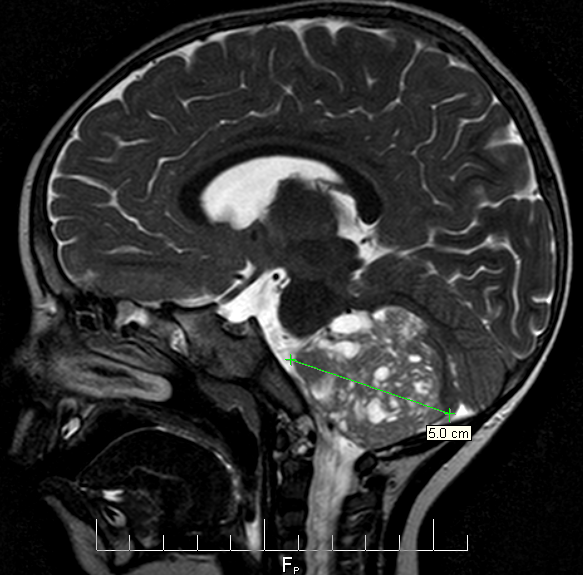

At Sick Kids we were seen by Dr. Audrey Segal who was the first person to truly listen to our story and patiently note all the details, and she ordered some bloodwork and a CT scan. By around 10:30pm, Audrey had to break the devastating news that Gavin had a large posterior fossa brain tumour.

About 3 weeks later we received the final diagnosis from the pathology team: Cribriform Neuroepithelial Tumor (CRINET) which is a variant of Atypical Teratoid Rhabdoid Tumor (AT/RT). AT/RT is a rare, aggressive cancer with a low survival rate, but CRINET has a slightly better prognosis. CRINET has only recently been identified so the case history (only 2 children at the time) makes it difficult to know how Gavin will fare. The other two children are long-term survivors, but were initially misdiagnosed and treated with protocols designed for other tumour types.